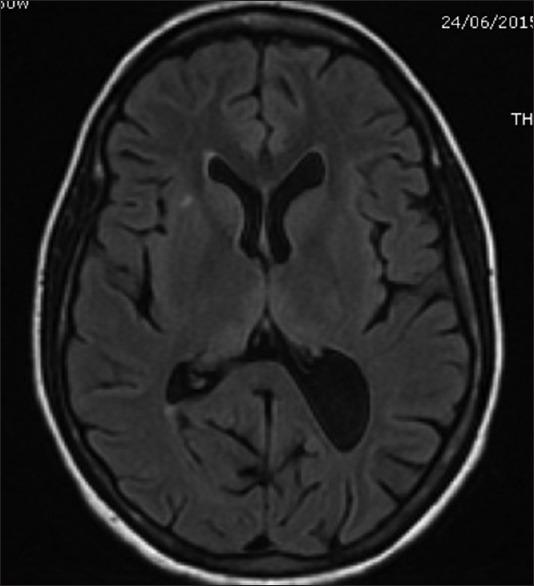

Hyperemesis gravidarum-induced Wernicke's encephalopathy (WE) is an underestimated condition. The purpose of this study is to improve its awareness and early diagnosis. We report five cases of WE secondary to hyperemesis gravidarum. Classic triad of encephalopathy, ataxia, and ocular signs was seen in four out of five patients. Two unusual features noted in this series were papilledema in one patient and severe sensory-motor peripheral neuropathy in one patient. Magnetic resonance imaging (MRI) was abnormal in all the five patients, and high signal in medial thalamus and surrounding the aqueduct was the most common abnormality (5/5). Involvement of caudate nucleus was seen in two patients with severe psychosis, and two patients had bilateral cerebellar peduncle involvement. Median time delay between onset of neurological symptoms and diagnosis was 7 days. All patients improved with thiamine, but minor sequelae were seen in four patients at 12 months follow-up. One patient had a fetal demise. Hyperemesis gravidarum-induced WE is a common cause of maternal morbidity. Typical MRI findings of symmetric medial thalamic and periaqueductal signal changes may permit a specific diagnosis. A delay in diagnosis, therefore treatment, leads to worse prognosis.

妊娠剧吐所致韦尼克脑病(WE)是一种被低估的疾病。本研究的目的是提高对其的认识并实现早期诊断。我们报告了5例继发于妊娠剧吐的韦尼克脑病病例。五分之四的患者出现了脑病、共济失调和眼部体征的典型三联征。本系列中注意到的两个不寻常特征是1例患者出现视乳头水肿,1例患者出现严重的感觉运动性周围神经病。所有5例患者的磁共振成像(MRI)均异常,内侧丘脑和导水管周围高信号是最常见的异常表现(5/5)。2例严重精神病患者出现尾状核受累,2例患者双侧小脑脚受累。神经症状出现至诊断的中位时间延迟为7天。所有患者经硫胺素治疗后均有改善,但在12个月的随访中,4例患者出现轻微后遗症。1例患者发生胎儿死亡。妊娠剧吐所致韦尼克脑病是孕产妇发病的常见原因。对称的内侧丘脑和导水管周围信号改变的典型MRI表现可能有助于做出明确诊断。诊断延迟进而导致治疗延迟会导致预后更差。